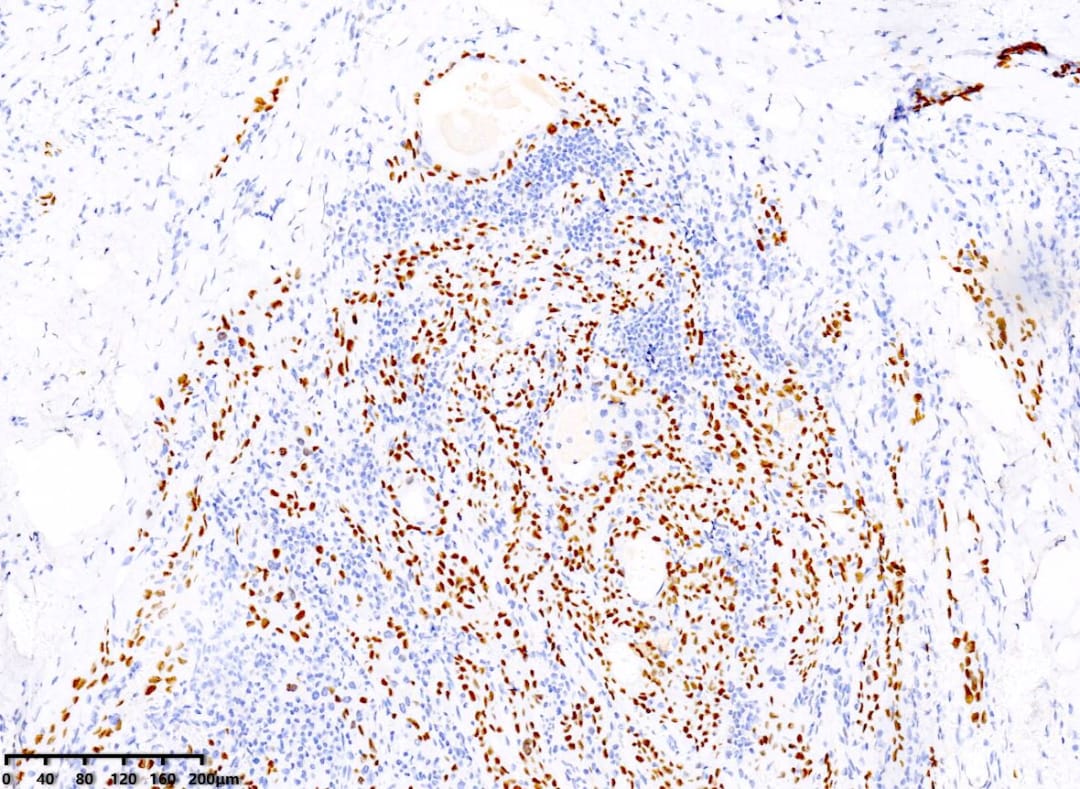

CK5/6(+)

p40(+)

P63(+)

免疫组化结果显示:CK19(+)、p40(+)、p63(+)、PAX8(+)、TTF-1(+)、CK5/6(+)、CyclinD1(+)。值得注意的是,BRAF V600E(部分+)和p53突变型阳性,Ki67阳性指数约15%。这些分子标记物对于确诊和鉴别诊断至关重要。